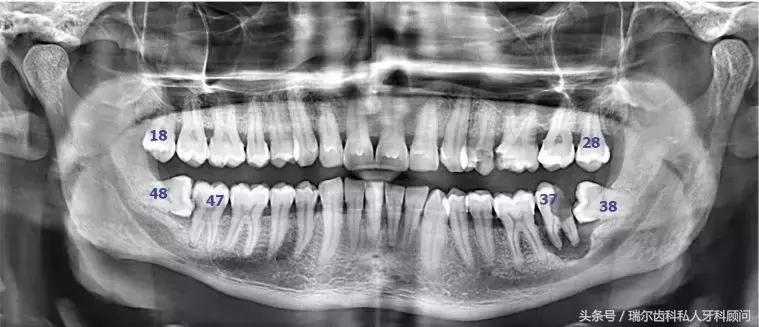

当你觉得自己没有智齿的时候,千万别高兴太早,有可能,你的智齿只是被埋在牙槽骨里了而已,我们肉眼看不到,在他们搞出事情之前,想要发现它们需要拍牙片。而且这种躲在暗处,搞破坏于无形的智齿才最可怕,所以,每年定期做好口腔检查能花小钱办大事,就像体检一样,防患于未然。

智齿是人类的第三磨牙(从中间门牙往里数第八颗就是),一般在20岁左右萌出,这时候人的生理、心理发育趋于成熟,所以俗称为“智齿”。